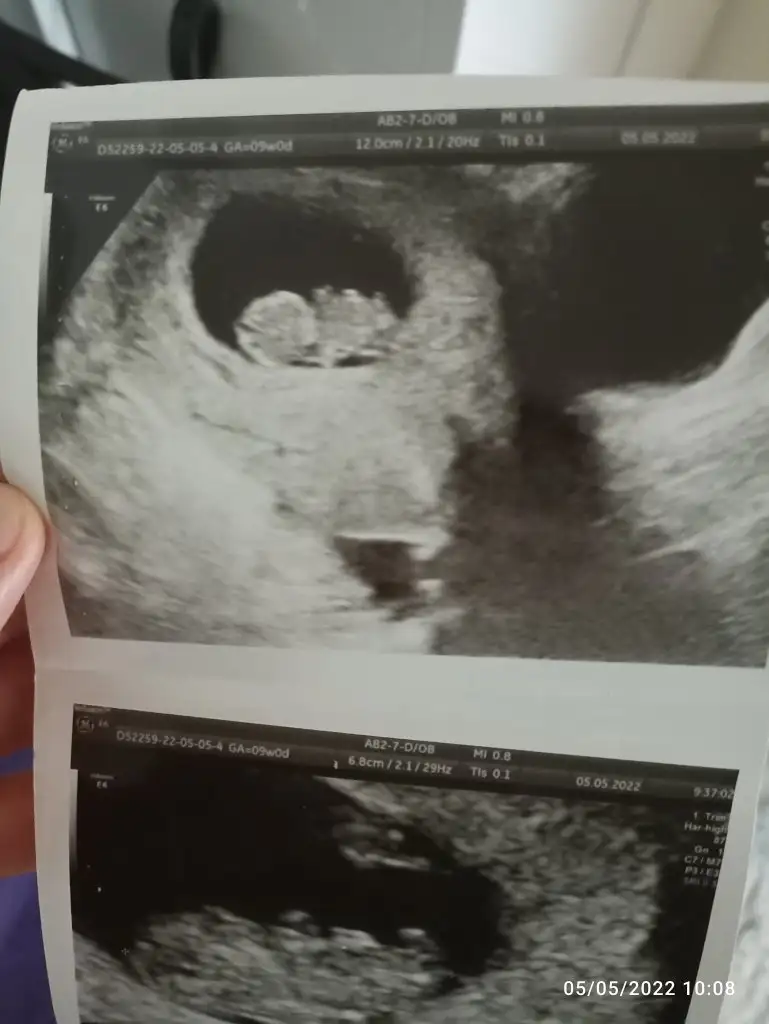

9+1 karından ultrason ile çekildi. Çok teşekkür ederim. Sevgiler.

paşa gibi 7 haftalık görüntüsü var mı?Merhaba Nur hanım rica etsem bana da bakar mısınız 9+0 karından